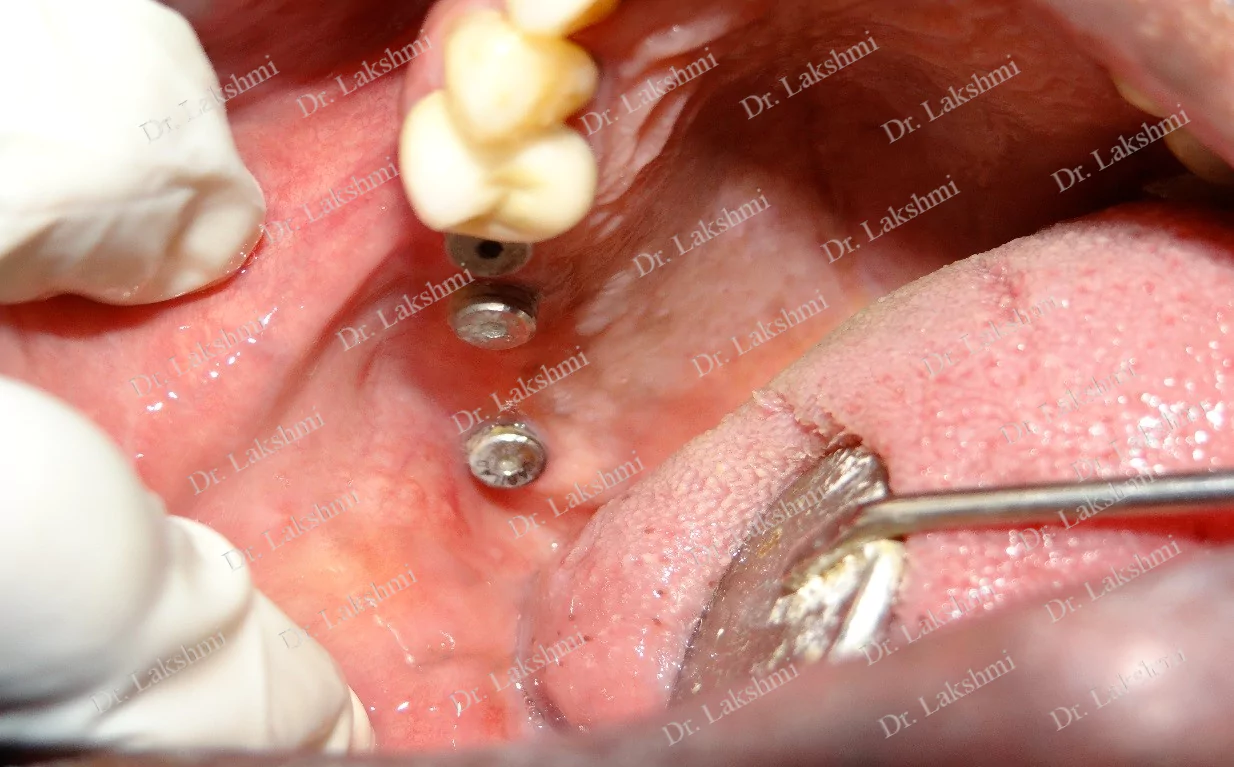

Multiple Tooth Replacement : Entirely depends on number of missing teeth.Either same number of Implants or fewer number of Implants than missing teeth can be placed. For example patient with 4 missing teeth ,we can place 2 Implants followed by a 4units bridge.

Treatment Duration: 2 stage dental implants: The replacement is completed in 2 stages which are spread over an interval of minimum 3 months. The first stage involves the placement of the implant and requires one to two sittings,Temporary Crowns will be given to the patient. The second stage involves the placement of the artificial tooth (Permanent crown).

1 stage dental implant: Requires just one stage for the placement of the implant and crown(Permanent Crown).